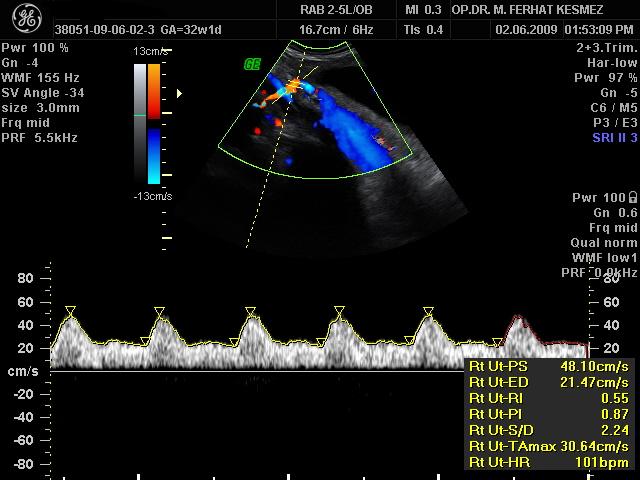

Ultrason Ölçümleri